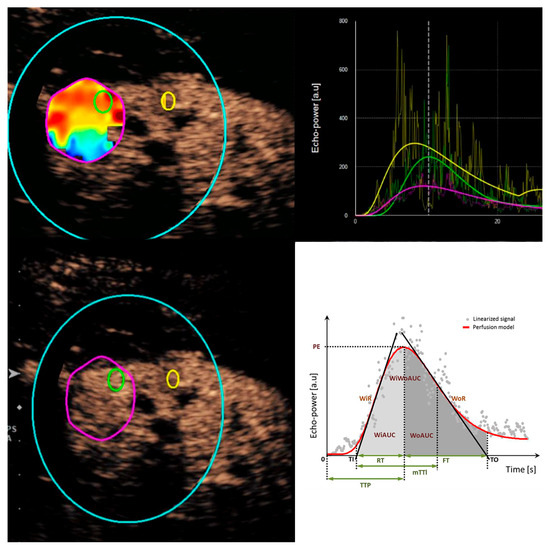

2.2. Image Acquisition and Analysis

- Wiesinger, I.; Jung, F.; Jung, E.M. Contrast-enhanced ultrasound (CEUS) and perfusion imaging using VueBox®. Clin. Hemorheol. Microcirc. 2021, 78, 29–40. [Google Scholar] [CrossRef] [PubMed]

- Dietrich, C.F.; Correas, J.M.; Cui, X.W.; Dong, Y.; Havre, R.F.; Jenssen, C.; Jung, E.M.; Krix, M.; Lim, A.; Lassau, N.; et al. EFSUMB Technical Review—Update 2023: Dynamic Contrast-Enhanced Ultrasound (DCE-CEUS) for the Quantification of Tumor Perfusion. Ultraschall Der Med. Eur. J. Ultrasound 2024, 45, 36–46. (In English) [Google Scholar] [CrossRef] [PubMed]